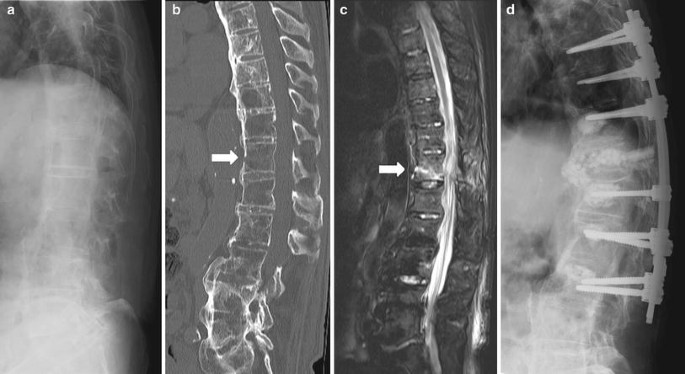

Get Fractured Spine In Elderly Pics. If you're female and over 70, you may know the pain and inconvenience of an osteoporotic fracture. If there is a fracture, along with nerve or spinal cord compression, decompression and fixation are required with cement augmented screws and rods.

The goals of surgical stabilization of thoracic and lumbar. Hip fractures in elderly adults can be serious. Geriatric fractures or fractures in elderly people is a special category of fractures in adults. These fracture demand a special category because of he works in kanwar bone and spine clinic, dasuya, hoshiarpur, punjab.